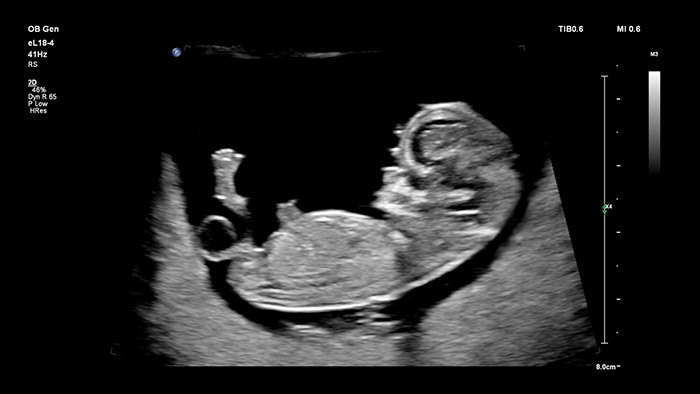

Transductor eL18 -4 de Philips

Resolución y penetración del máximo nivel:

El transductor eL18 -4 de Philips con MicroFlow Imaging salva todos los obstáculos gracias a la adquisición de imágenes 2D de alta resolución y a la detección ultrasensible del flujo sanguíneo; estos elementos están pensados para evaluar el estado de salud general del feto en las primeras etapas del embarazo, momento en el que una resolución excelente y un diagnóstico fiable resultan determinantes. El transductor V9-2, muy versátil y está específicamente diseñado para obstetricia; emplea la potencia de la tecnología PureWave Crystal para ofrecer unas imágenes 2D y 3D óptimas; no obstante, también es ligero en comparación con otros de su categoría.